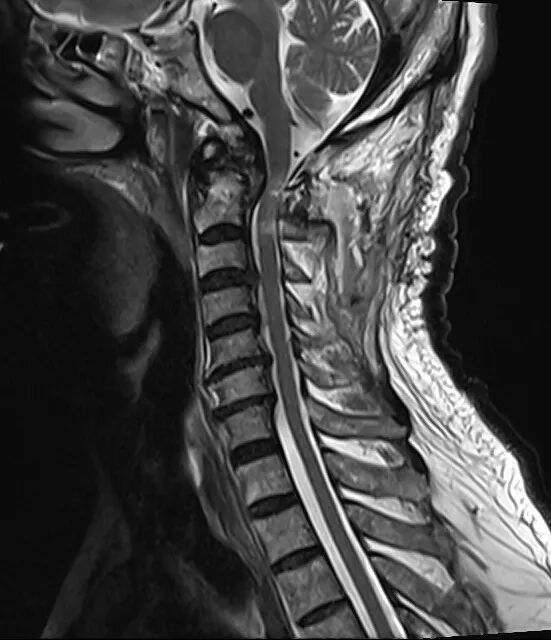

▲术后

手术全程顺利、创伤小、出血少,术后患者颈部疼痛明显缓解,肢体功能逐步改善,生命体征平稳,康复进展顺利。老人及家属连连致谢:“赶在春节前治好病,终于能过个安稳年了!